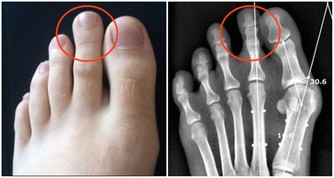

第一、減少尿酸生成

減少尿酸的生成,在生活中主要體現在飲食的調整上,不單單要限制高嘌呤食物的攝入,比如少吃或者不吃海鮮、動物的內臟,少和白酒啤酒等,還要少吃高糖、高脂肪的食物。因為血樣、血脂和血尿酸之間具有相互促進的作用。